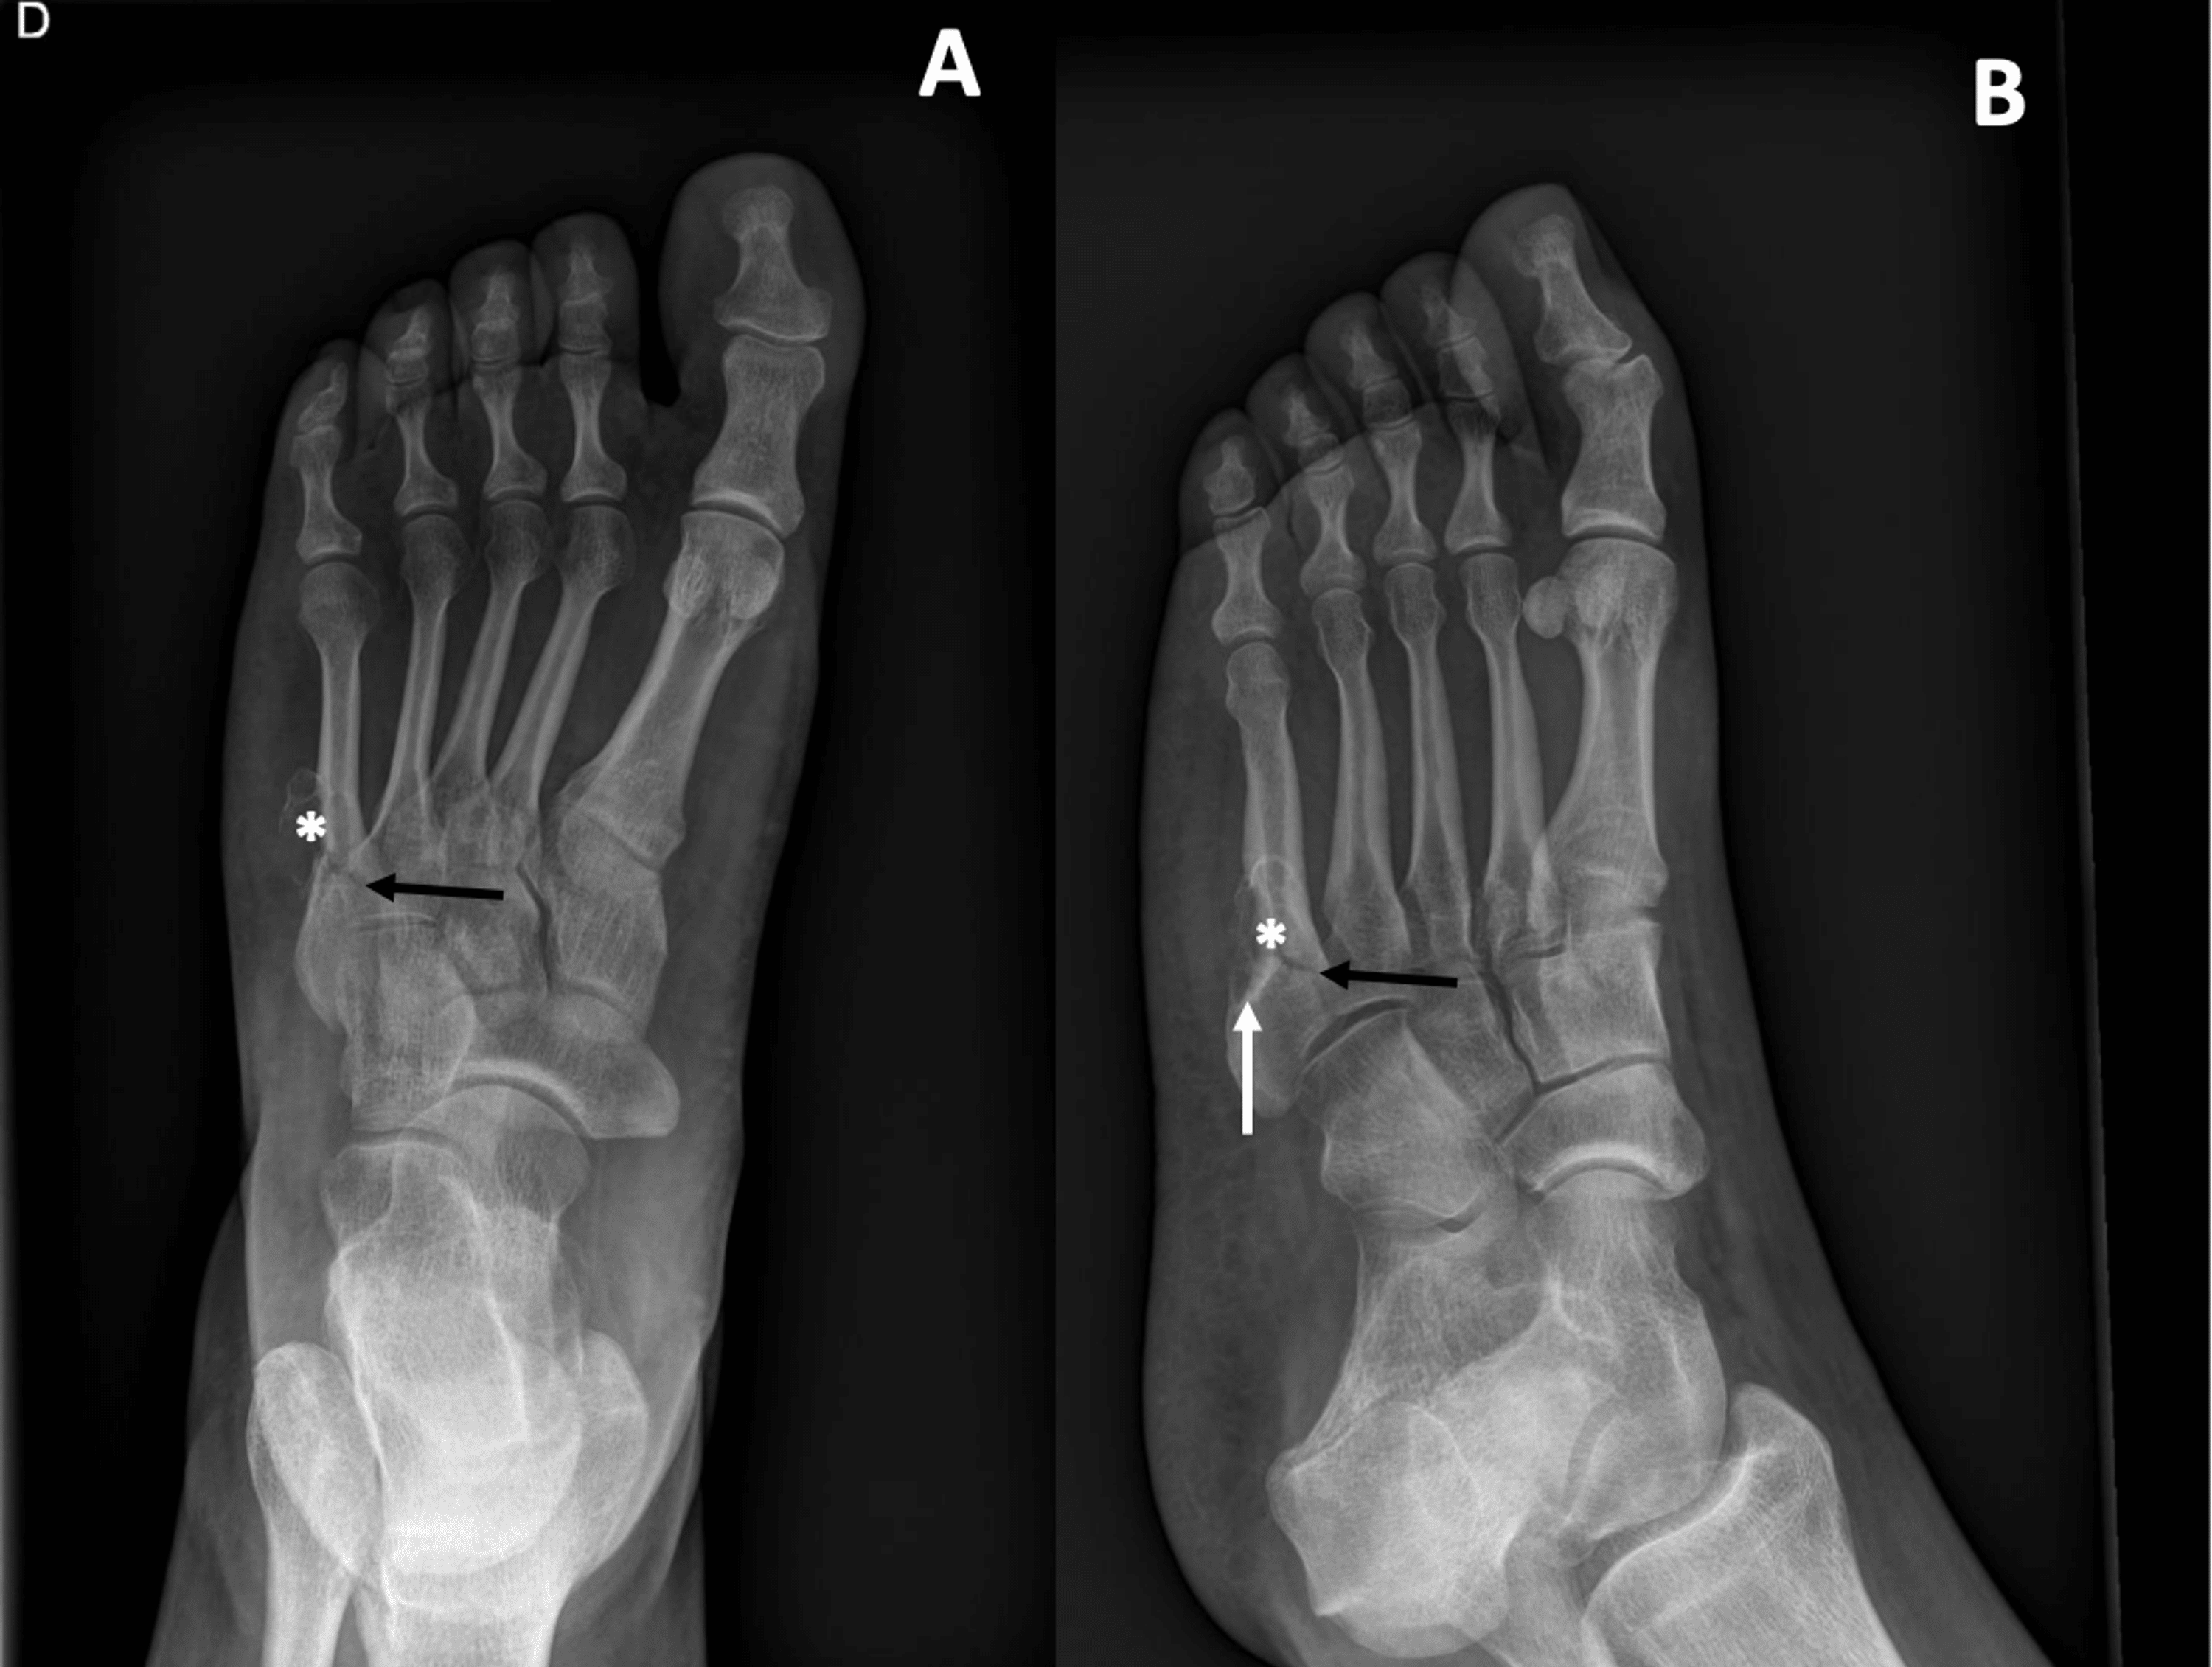

Gout with Multiple Large Tophi Especially in the First Metatarsal

Cureus A Case of a Second Intermetatarsal Space Gouty Tophus with a Gout Foot Metatarsal gout is a form of arthritis that causes sudden, severe attacks of pain, swelling and inflammation in one or more joints, often in the big toe. gout, a crystalline arthropathy caused by the deposition of monosodium urate crystals in the articular and periarticular soft. gout is a form of arthritis that causes pain and swelling in your. Gout Foot Metatarsal.

A anteroposterior radiograph of the feet of a patient with gout Gout Foot Metatarsal Podagra is the term for gout affecting the first. gout, a crystalline arthropathy caused by the deposition of monosodium urate crystals in the articular and periarticular soft. podagra, which in greek translates to ‘foot trap’, is gout which affects the joint located between the foot and the big. gout is a form of arthritis that causes sudden,. Gout Foot Metatarsal.

Gout. Anteroposterior foot radiograph shows multiple punchedout Gout Foot Metatarsal Podagra is the term for gout affecting the first. Often occurs during sleep, and may go on to involve more than one joint, becoming an oligoarthropathy or rarely, a polyarthropathy. gout is a form of arthritis that causes sudden, severe attacks of pain, swelling and inflammation in one or more joints, often in the big toe. podagra, which. Gout Foot Metatarsal.